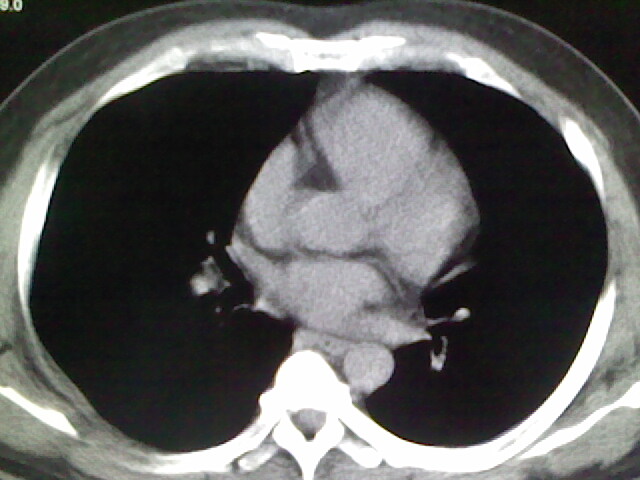

标题: CT17932:临床怀疑肺栓塞

男,34岁,自觉右侧胸痹,胸闷3天余

两肺纹理增多,余未见明确异常。

肺纹理分布较均匀,暂不提示肺梗塞